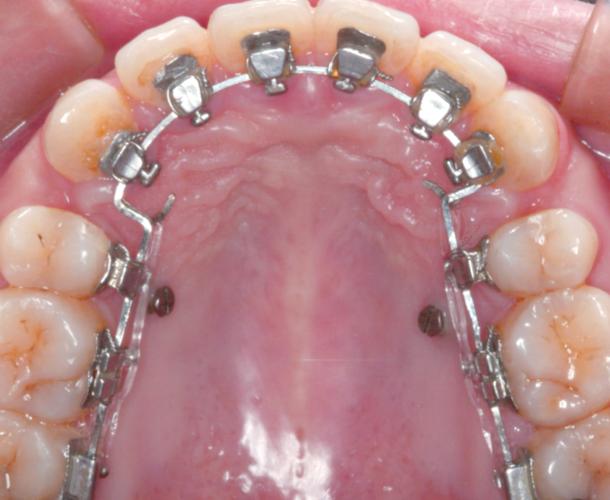

正畸方形勾托槽-图1

(图片来源网络,侵删)